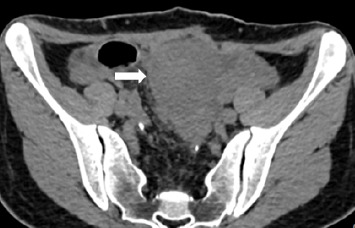

A variation of familial adenomatous polyposis (FAP), known as Gardner's syndrome (GS), can manifest as extraintestinal tumors, such as desmoid tumors (DTs). A key part in the diagnosing process is played by the clinician. Because DT frequently occurs before intestinal polyposis develops, doctors can identify the underlying illness early by looking for DT's telltale signs. Nevertheless, in this instance, the patient's failure to recognize the illness promptly following the excision of the tumor in the abdomen wall caused a delay in the diagnosis and impacted the disease's course.